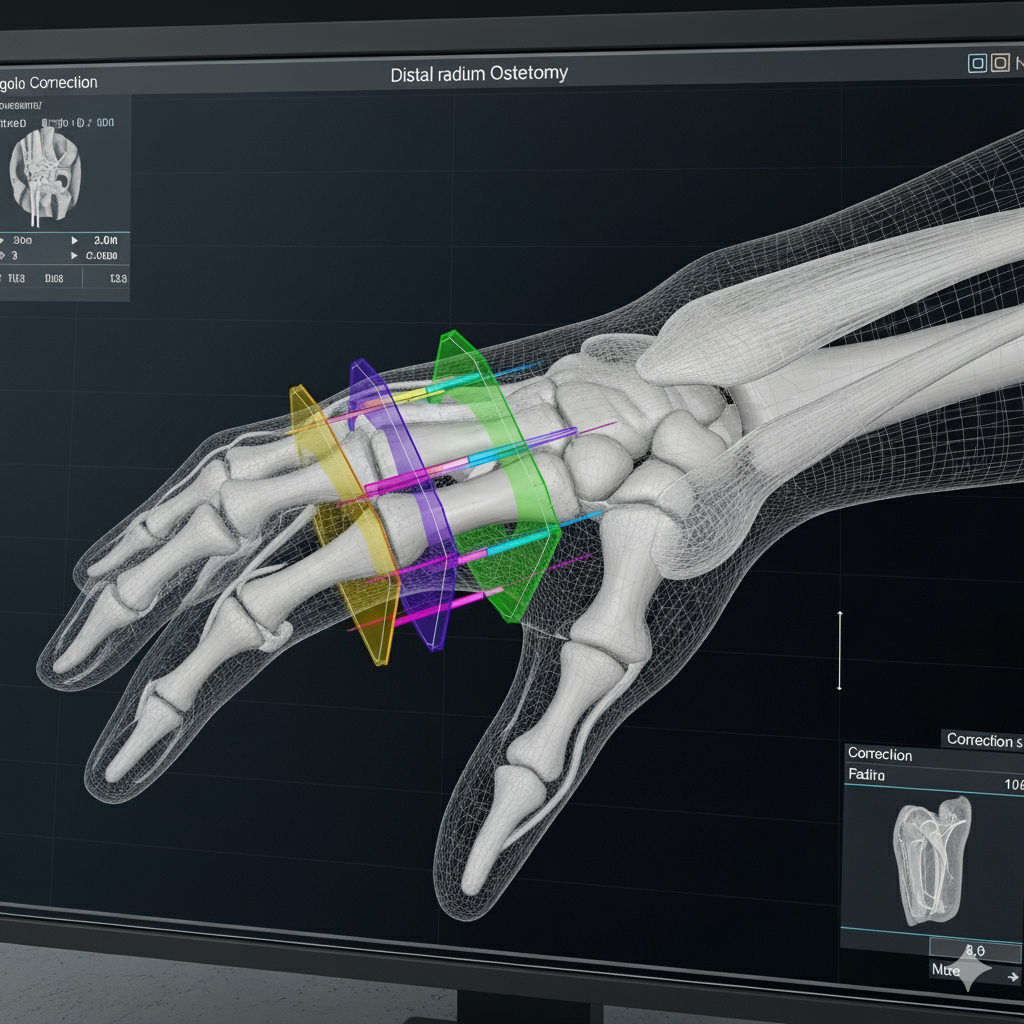

Implantes personalizados en 3D

Ofrecemos una solución avanzada y a medida para fracturas y deformidades. Diseñamos implantes 3D que se adaptan con precisión a tu anatomía, garantizando una recuperación más rápida y un resultado funcional superior.